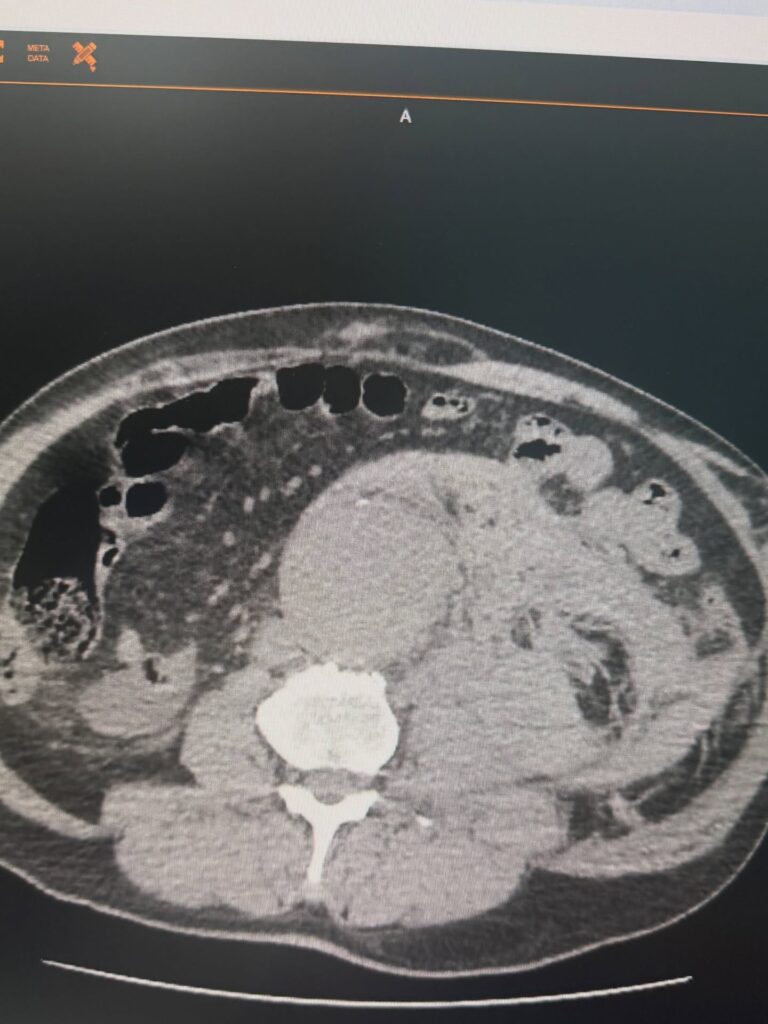

У судинному центрі Черкаської обласної лікарні успішно проведено лікування пацієнта з розривом аневризми черевної аорти. Повідомив у Фейсбуці судинний хірург Артем Губенко.

Розрив аневризми – один з найнебезпечніших ургентних станів у судинній хірургії. Це ситуація, де рахунок іде на хвилини, а кожне рішення має критичне значення.